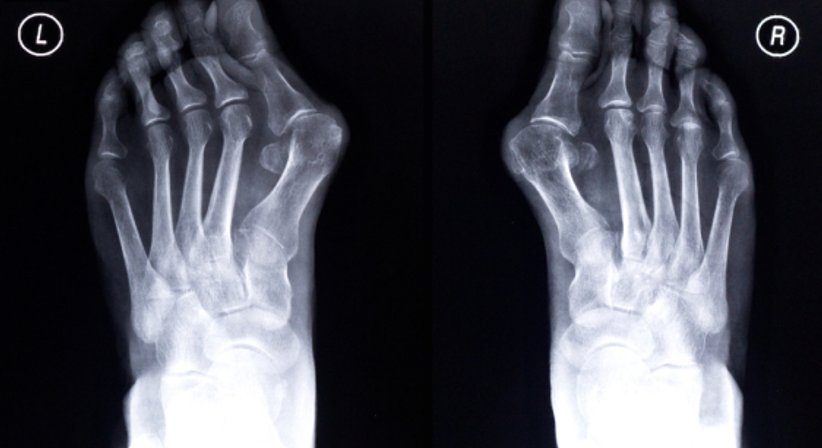

Bei einem Hallux valgus handelt es sich um eine Fehlstellung der Großzehe, bei welcher sich der Mittelfußknochen nach außen richtet, während sich die Großzehe in Richtung der mittleren Zehen bewegt. In den meisten Fällen sind dauerhafte Fehlbelastungen des Fußes die Ursache für die Fehlstellung.

Bei einer fortgeschrittenen Fehlstellung wird eine korrigierende Osteotomie durchgeführt. Dabei wird der nach innen gespreizte erste Mittelfußknochen V-förmig durchtrennt und anschliessend in seine ursprüngliche Position verschoben. Überstehendes Gewebe wird entfernt. Abhängig vom Grad der Fehlstellung und der Anatomie des Fußes werden in manchen Fällen Schrauben eingebracht, um die Knochendurchtrennung zu stabilisieren. Begleitend können auch Hammerzehen durch einen kleinen Eingriff korrigiert werden.